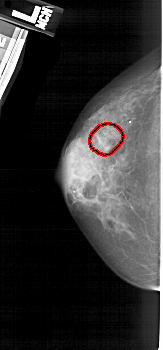

A_1937_1.RIGHT_CC

RIGHT_CC LINES 4576 PIXELS_PER_LINE 2251 BITS_PER_PIXEL 12 RESOLUTION 43.5 NON_OVERLAY

FILE: A_1937_1.LEFT_MLO.OVERLAY

TOTAL_ABNORMALITIES 1

ABNORMALITY 1

LESION_TYPE CALCIFICATION TYPE PLEOMORPHIC DISTRIBUTION CLUSTERED

ASSESSMENT 4

SUBTLETY 3

PATHOLOGY BENIGN

TOTAL_OUTLINES 1

BOUNDARY